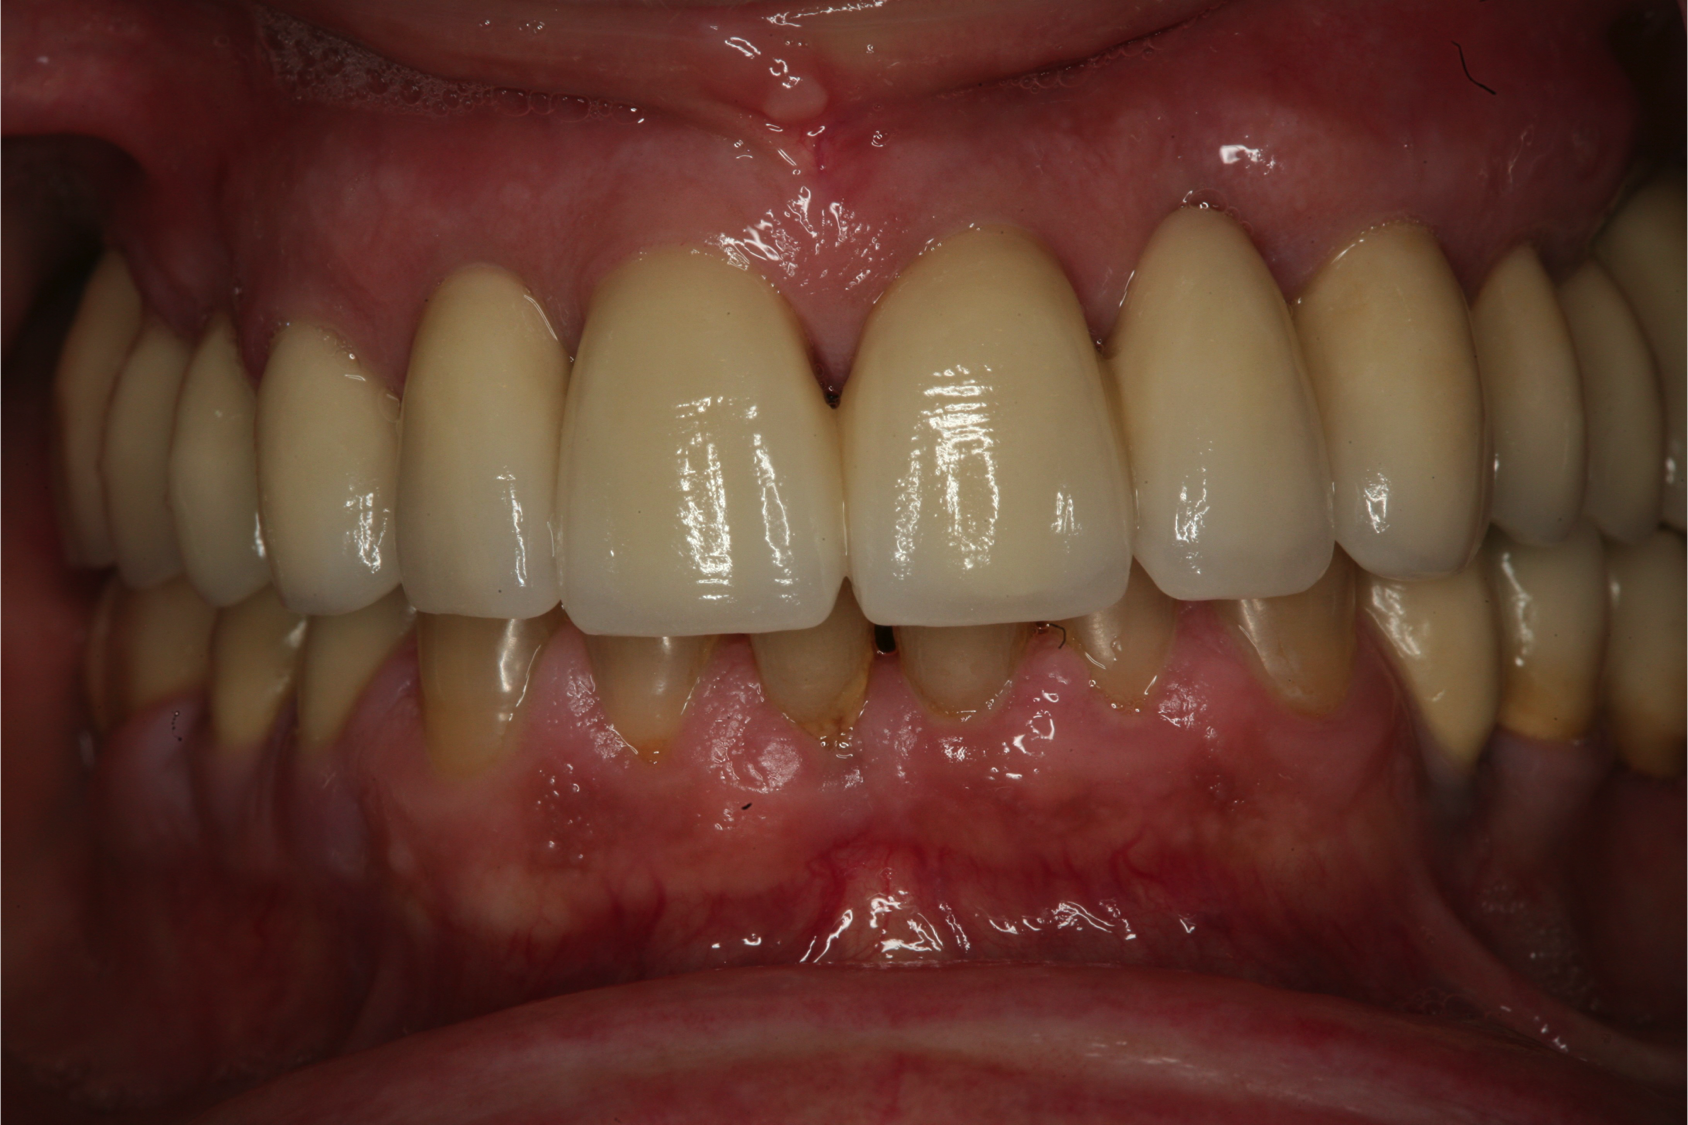

Fig 12. Frontal view (Fig 12) and occlusal view (Fig 13) of clinical application of dual-axis principles. (Images courtesy of Costa Nicolopoulos, BDS)

Figure 12

Fig 13. Frontal view (Fig 12) and occlusal view (Fig 13) of clinical application of dual-axis principles. (Images courtesy of Costa Nicolopoulos, BDS)